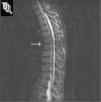

En las pruebas de laboratorio destacaba: hemoglobina, 11,6g/dl (12–15); volumen corpuscular medio, 83,20fl (78–100); velocidad de sedimentación globular, 25 (0-20), y PCR, 5,4mg/l (0–5). La bioquímica, el proteinograma y el sistemático de orina fueron normales. El PPD fue positivo (11mm), con radiografía de tórax normal. Los hemocultivos, la serología de Brucella y los bacilos ácido-alcohol resistentes en orina resultaron negativos. La paciente aportaba radiografía de columna lumbar en la que se apreciaba acuñamiento anterior de D12, no visto en placas previas, osteopenia y cuadratura de los cuerpos vertebrales. Se completó el estudio con una resonancia magnética (RM) de columna dorsal STIR (fig. 1) que mostraba una imagen hiperintensa en T2 con supresión grasa compatible con una lesión de Anderson de grado C1 (edema en cuerpo vertebral) a nivel de D7 y D8; una lesión hiperintensa en T2 a nivel de L1-L2 compatible con una lesión de Anderson grado C2 (recambio graso) y un acuñamiento anterior osteoporótico a nivel de D12 sin signos de edema. Se realizó también una densitometría ósea que mostraba datos de osteopenia lumbar (T-score, -2,2; Z-score, -0,86) y femoral (T-score, -1,8; Z-score, -0,62).

Resonancia magnética de columna dorsal, corte sagital con secuencia STIR: muestra una imagen hiperintensa en T2 compatible con una lesión de Anderson de grado C1 (edema en cuerpo vertebral) a nivel de D7 y D8; una lesión hiperintensa a nivel de L1-L2 compatible con una lesión de Anderson grado C2 (recambio graso) y un acuñamiento anterior osteoporótico de D12 sin signos de edema.